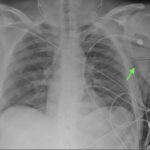

Plain film anteroposterior (AP) radiography of the chest shows left-sided subcutaneous emphysema (red arrow) with overlapping muscle striations of the pectoralis major (green arrow). After chest tube placement (blue arrow), AP chest radiography shows persistent left-sided subcutaneous emphysema (red arrow). CT of the chest shows pneumomediastinum (blue arrow), left apical pneumothorax (pink arrow), and subcutaneous emphysema (red arrow) at the level of T2. At the level of T6, rib fractures can be visualized on the CT (yellow arrow). At the level of T8, left sided pneumothorax is also seen (pink arrow) as the absence of lung tissue on CT.